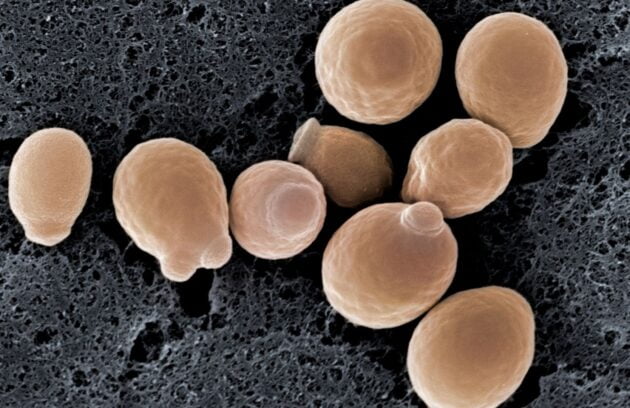

Biorezonans ile Kandida Tedavisi

Kandida mantarı biorezonans ile tedavi edilebiliyor Virüs (korona, herpes, hepatit, influenza vb.) enfeksiyonları, bakteri (streptokok, pnömokok, e.coli vb.) enfeksiyonları, mantar…